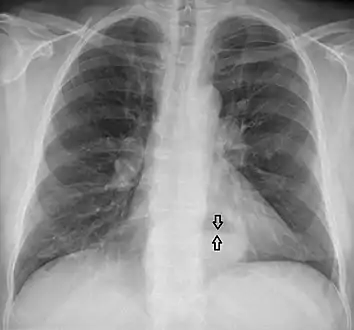

The diagnosis of a hiatal hernia is typically made through an upper GI series, endoscopy, high resolution manometry, esophageal pH monitoring, and computed tomography (CT). Barium swallow as in upper GI series allows the size, location, stricture, stenosis of oesophagus to be seen. It can also evaluate the oesophageal movements. Endoscopy can analyse the esophageal internal surface for erosions, ulcers, and tumours. Meanwhile, manometry can determine the integrity of esophageal movements, and the presence of esophageal achalasia. pH testings allows the quantitative analysis of acid reflux episodes. CT scan is useful in diagnosing complications of hiatal hernia such as gastric volvulus, perforation, pneumoperitoneum, and pneumomediastinum.[8]